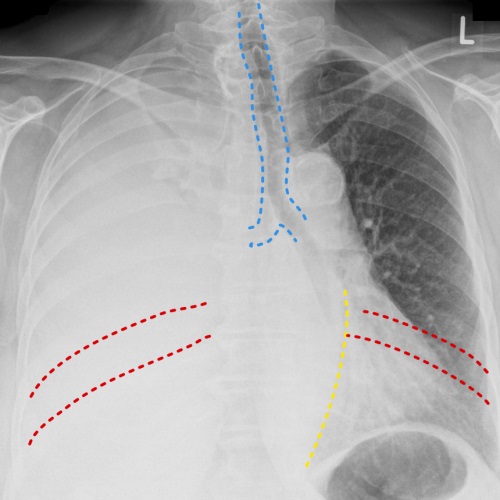

Pleural effusion - note how the trachea (blue) is pushed away the side of the white-out. The other signs of a positive mass effect include leftward bowing of the azygo-oesophageal recess (yellow) and splaying of the ribs on the right (red)